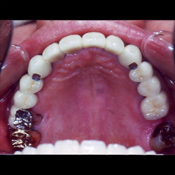

60代 男性 下顎左右の奥歯に5本のインプラントを埋入し、上下顎全歯牙をメタルボンドセラミッククラウン(白い歯)にて審美修復を実施。

審美的な最終構造物メタルボンドセラミッククラウン(白い歯)を全歯牙に装着した写真です。

人工歯の色あいは、ご年配の方であることを考慮し加工してあります。